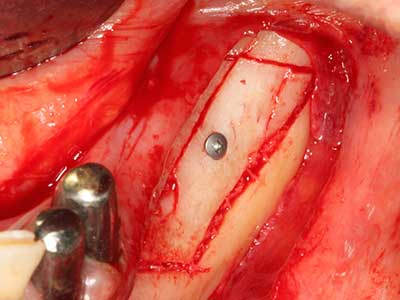

Пиезохирургията има допълнителни предимства при събиране на костни блокове. В допълнение към високата прецизност при остеотомията, описана по-горе, употребата на фините режещи накрайници значително намаляват загубата на материал. Голяма загуба на материал по време на събиране може да се очаква с дебелите накрайници, особено при употреба на борери Линдеман (Lakshmiganthan, Gokulanathan et al. 2012). Базалното разделяне, което е необходимо, особено за присадка на блок при ретромолар, е улеснено от специално създадени правоъгълни триони. В резултат на това, пиезохирургията е разглеждана като прецизна, улеснена и безопасна процедура за събиране на костни блокове в ретромоларното пространство (Happe 2007) (Фиг. 1-12).

Както е показано в миналото, всяка костна хирургия представлява възможна индикация за пиезохирургия. По този начин, за препарацията на подвижни сегменти в остеогенеза (Фиг. 23-25) и остеотомия се използват специални накрайници, без да се застрашава снабдяването с кръв в кресталната зона, което е от съществено значение за успеха и на двете техники (Gonzalez-Garcia, Diniz-Freitas et al. 2008).